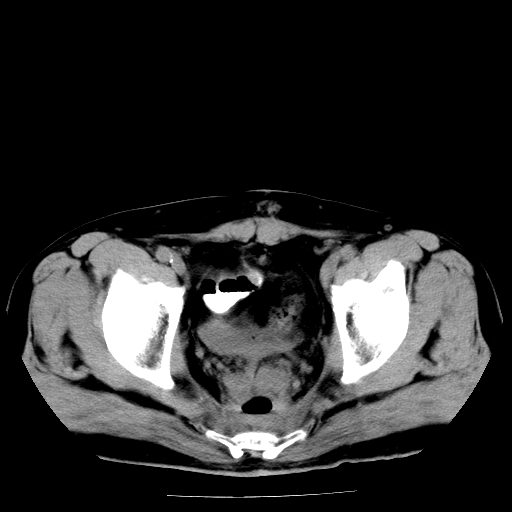

男,66岁,直肠癌术后一个月,化疗前ct检查。

膀胱充盈不太好,前列腺较大,前列腺肥大?占位?建议:结合临床.

前列腺大,直肠壁厚,造瘘术后

前列腺肥大

直肠癌造瘘术后改变,直肠周围软组织增厚,盆腔多发淋巴结转移。前列腺肥大。

前列腺肥大。